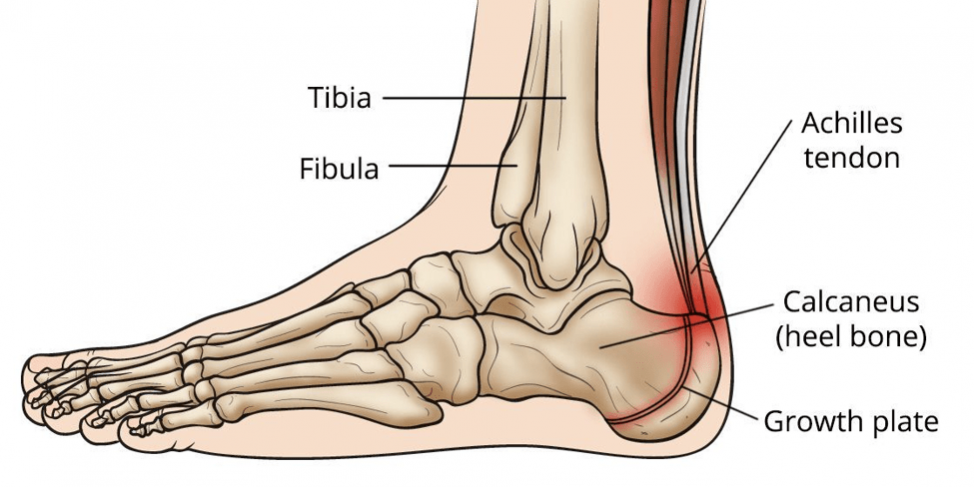

Ankle and foot